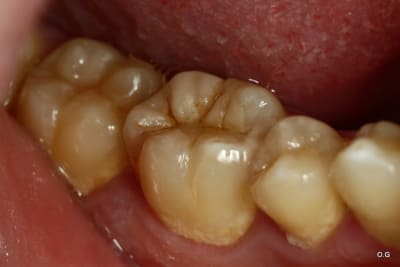

Onlay emax à 5 ans... contrôle la semaine dernière...

Dans cette situation, que donnerait un composite ?

tiens c'est bizarre , sur la dernière photo de cingulum (magnifique travail d'ailleurs) , la dent est toujours sur l'arcade alors que le joint semble être juxta voir sous gingival. Il m'a semblé avoir lu plus haut qu'un joint en compo ça se carie automatiquement au bout de cinq ans....

C'est très beau...

Mais je dois admettre que dans ce cas... Des IC-CCM aux limites un peu sous-gingivales qui tiennent 30 ans on en voit aussi. Dans ce cas précis je ne suis pas certain que ce soit préférable (collage), que se passera-t-il si reprise de carie? La limite sera très certainement trop sous gingivale et la couronne ne sera probablement pas réalisable (même si c'est au bout de 15 ans). Vu le reste à charge supérieur et la forte probabilité d'avoir à extraire en cas d'échec, ne valait-il pas mieux utiliser une technique pour laquelle on a énormément de recul?

Sinon je suis fan des collages puisque effectivement même si échec à 10 ans il y a on pourra à ce moment-là sortir l'artillerie lourde.